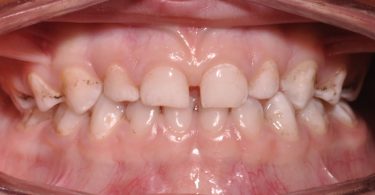

T.G., paciente do sexo masculino, com quatro anos de idade, dentição temporária completa, sem antecedentes médicos relevantes e com história prévia de falta de colaboração nas consultas de medicina dentária.

Foi realizado um exame clínico e radiológico inicial (fig. 1 a 3), tendo sido diagnosticada, entre outras lesões de cárie, uma lesão de cárie profunda com atingimento pulpar no segundo molar temporário inferior direito (fig. 3). Foi proposta a realização de uma pulpotomia com agregado trióxido mineral (MTA) e a colocação de uma coroa pré-formada. As várias possibilidades restauradoras foram apresentadas e discutidas com os pais, que decidiram optar pela colocação de uma coroa pré-formada de zircónia, por motivos estéticos.

Foi também sugerida a realização de sedação consciente devido à história prévia de falta de colaboração do paciente, tendo sido também aceite pelos responsáveis o recurso a esta técnica de controlo de comportamento, o que possibilitou a execução do plano de tratamento estipulado (fig. 4).